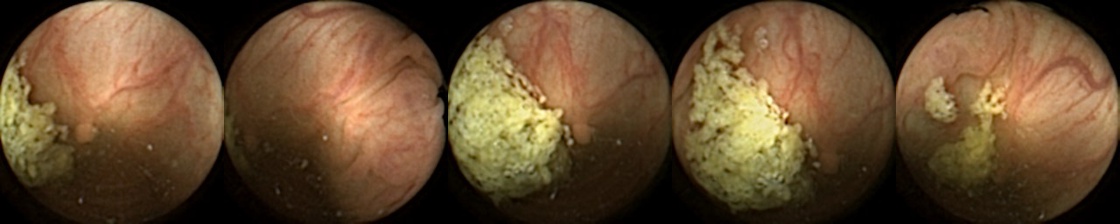

We can additionally consider the confusion matrices from the best MIV model associated with (a) the pretrained ConvNext and (b) SimCLR pretraining using the ConvNext backbone in Figure 5. We note that using SimCLR achieves a better ratio of False Negatives (70) to False Positives (38) as compared to pretrained ConvNext, which has 109 False Negatives and 23 False Positives.

Refer to caption

Figure 5: Confusion matrices from the best MIV model associated with (left) the pretrained ConvNext, and (right) SimCLR pretraining using the ConvNext backbone